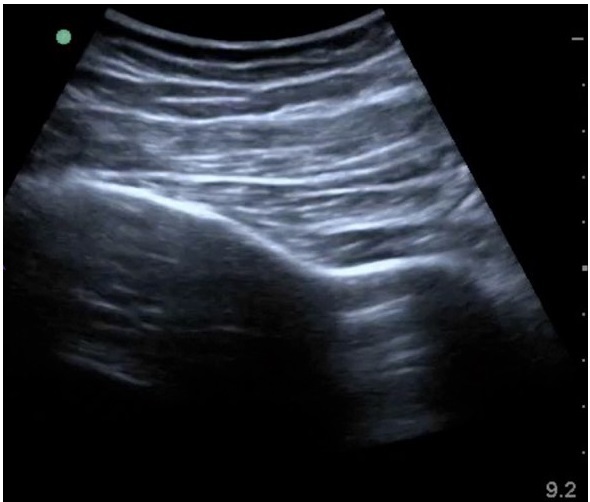

Ecografía del tensor de la fascia lata

<p>Tensor de la fascia lata</p>